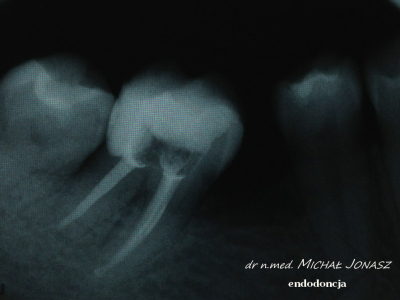

EXAMPLES OF ROOT CANAL TREATMENT PERFORMED BY OUR TEAM

Root canal treatment becomes necessary when the pulp of the tooth is attacked, that is, the tissue filling its interior, which is composed of blood vessels and lymphatic vessels as well as nerve fibers. In some cases, it happens that the tooth does not give pain, and yet there is an irreversible bacterial infection of the pulp. In most cases, patients requiring root canal treatment complain of acute pain in the affected teeth. Endodontic treatment is also necessary in some cases of tooth injury. This method of treatment is also sometimes used due to prosthetic indications. Infected dental pulp and pathological changes occurring in it are sometimes visible on the radiological image, which is performed before the procedure. Thorough cleansing, chemo-mechanical treatment of the root canal and its tight filling, for which special microscope is used, in the vast majority of cases leads to remission of bone changes and bone regeneration.